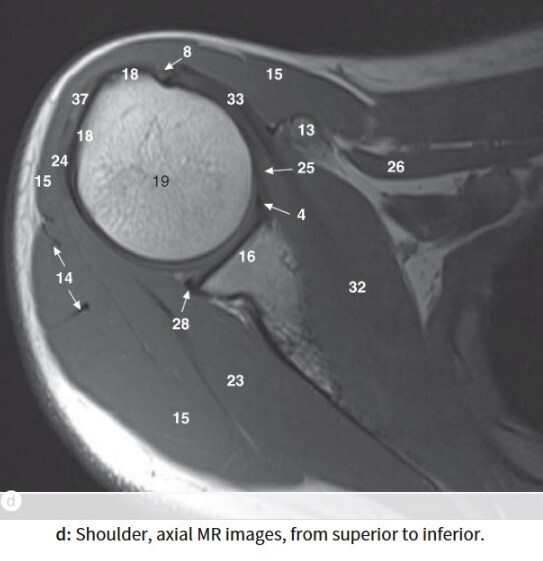

Label 13,15,16,18,19,23,32

A

13=Rt. coracoid process

15=Rt. deltoid muscle

16=Glenoid process of Rt. scapula

18=Greater tubercle of Rt. humerus

19=Head of Rt. humerus

23= Rt. infraspinatus muscle

32=Rt. subscapularis muscle